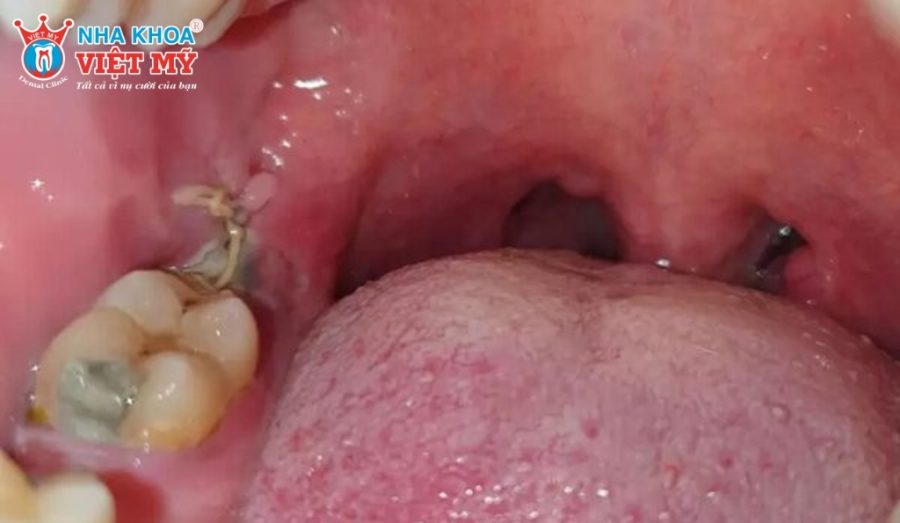

Xuất hiện mủ

Mủ màu vàng, trắng đục hoặc có mùi hôi xuất hiện tại vị trí nhổ răng là biểu hiện rõ rệt cho thấy vết thương đã bị nhiễm trùng. Nếu không xử lý kịp thời, ổ mủ có thể lan rộng, gây áp xe và ảnh hưởng nghiêm trọng đến các mô lân cận.

Dẫn lưu áp xe

Trong trường hợp nhiễm trùng đã hình thành ổ mủ, bác sĩ có thể tiến hành thủ thuật dẫn lưu áp xe. Đây là biện pháp giúp giải phóng mủ tích tụ trong mô nướu, giảm áp lực, giảm đau nhức và ngăn ngừa vi khuẩn lây lan. Sau khi dẫn lưu, bệnh nhân vẫn cần kết hợp dùng thuốc kháng sinh và chăm sóc răng miệng đúng cách để vết thương hồi phục nhanh chóng.